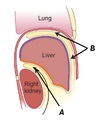

Name structure A

A - Lesser omentum